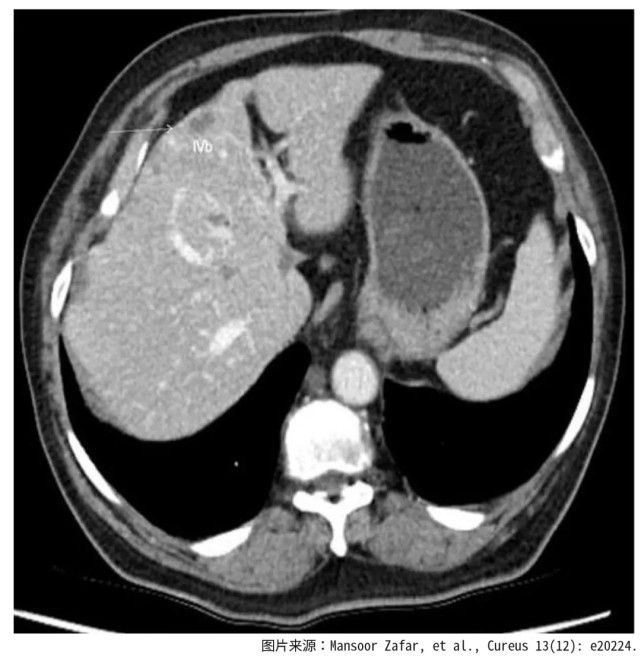

经过腹部超声检查发现肝部有转移性肿瘤,胃镜和CT扫描检查显示,胃小弯有大面积的恶性溃疡。活检证实为低分化腺癌。经过多学科会诊讨论之后,患者确诊为胃腺癌合并肝转移。

图片图1.腹部CT扫描显示胃癌已经转移至肝脏